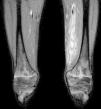

After three days of treatment, the patient persisted with the same symptoms showing no improvement. A soft tissue ultrasound reveled a dysfunctional muscle area in relation with the vastus medialis of quadriceps and the adductors muscles compatible with pyomyositis (Fig. 1). A MRI study confirmed the diagnosis (Fig. 2). Consequently, our department was consulted in order to consider surgical debridement. Finally he was taken to surgery performing a complete debridement and drainage of the muscle injury. Samples were collected and sent for microbiological study, identifying an infection due to E. coli as the causative agent.